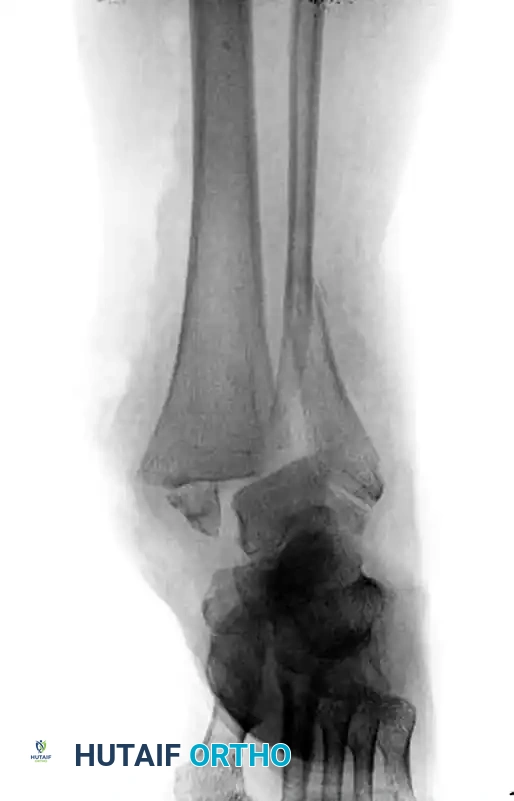

Consider the scenario of an elderly patient with osteoporosis, diabetes mellitus, and peripheral neuropathy who sustains an open comminuted bimalleolar ankle fracture-dislocation.

Preoperative radiograph demonstrating a highly unstable, comminuted bimalleolar fracture-dislocation in a neuropathic diabetic patient.